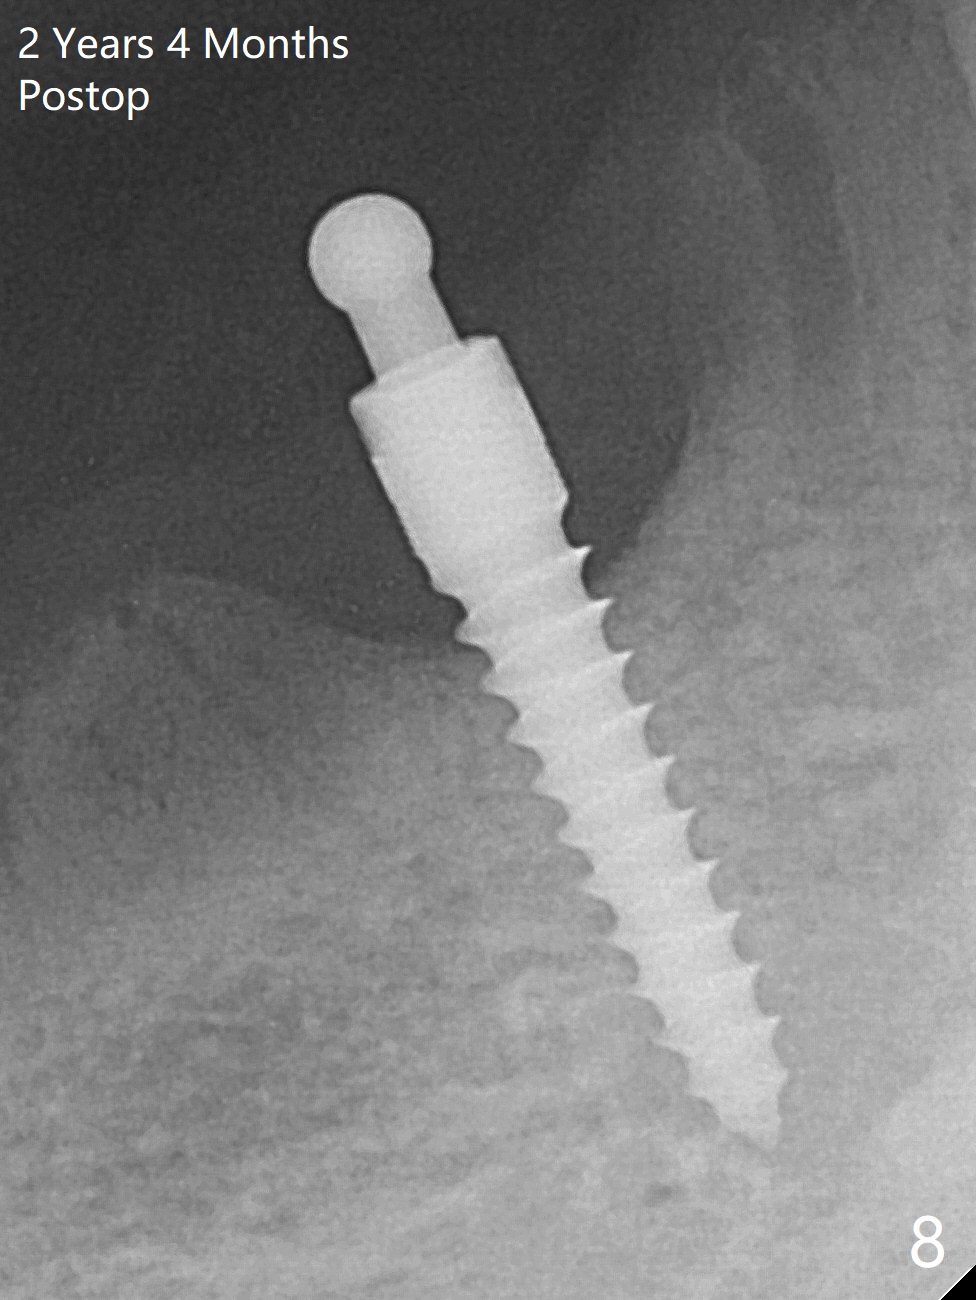

The ridge at #27 is narrow and is reduced ~ 4 mm in height (Fig.1 *) to obtain ~ 4 mm buccolingual width. A 3x14 mm 1-piece implant with ball abutment is placed (Fig.3 (*: bone graft)). In contrast, there is no problem of the buccolingual width after #22 extraction; initial osteotomy depth is 14 mm to gain ~ 5 mm of the native bone for primary stability (Fig.2). Since the lingual crest is significantly lower than the buccal one, a shorter implant (2-piece, 3.8x12 mm, Fig.4) is placed so that a ball abutment with a longer cuff is chosen (4 mm). Soft reline is applied to the site of #22 with minimal retention. But the patient is pleased with the "pain-free" procedure. It appears that gingivectomy is required for the ball abutments in 2 months (Fig.5). The implants seem osteotointegrated nearly 4 months postop (Fig.6,7). Ten months postop, the patient will return for fabrication of new full dentures to correct Class II relationship. There is mild or no bone loss 2 year 4 months postop (Fig.8,9), although the housing at #27 is dislodged. Return to Lower Canine Immediate Implant, Armaments Overdentures Xin Wei, DDS, PhD, MS 1st edition 07/24/2018, last revision 12/18/2020